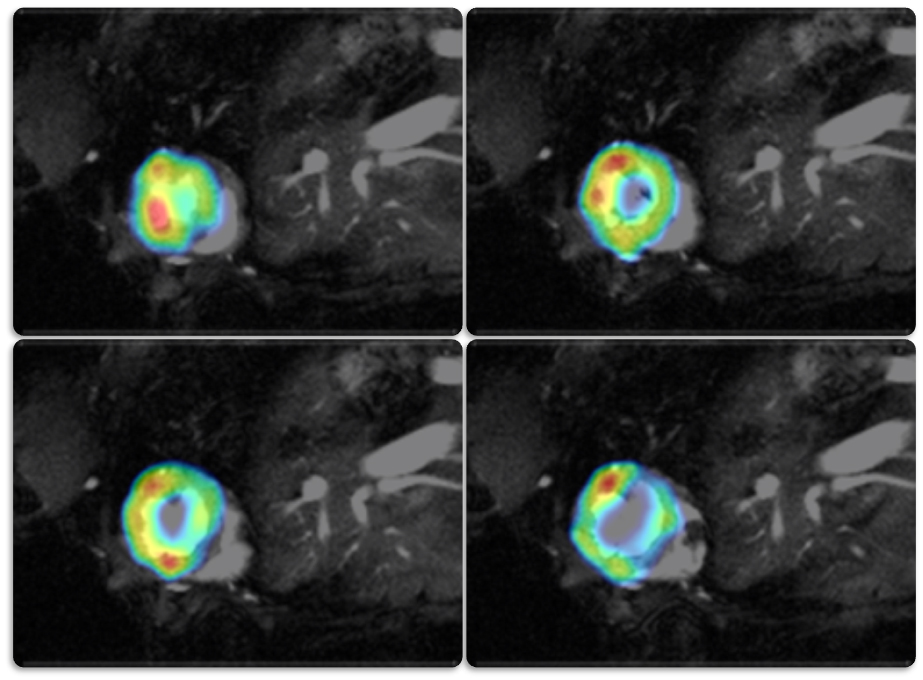

Restrospective Cardiac Gating

IntraGatePET improves quantification of cardiac data via retrospective gating using MR navigators.

Intrinsic synchronization of FDG PET and MRI cardiac data acquisition with IntraGatePET in mouse heart. Courtesy: W. Gsell, U. Himmelreich, C. Deroose, KU Leuven, Belgium